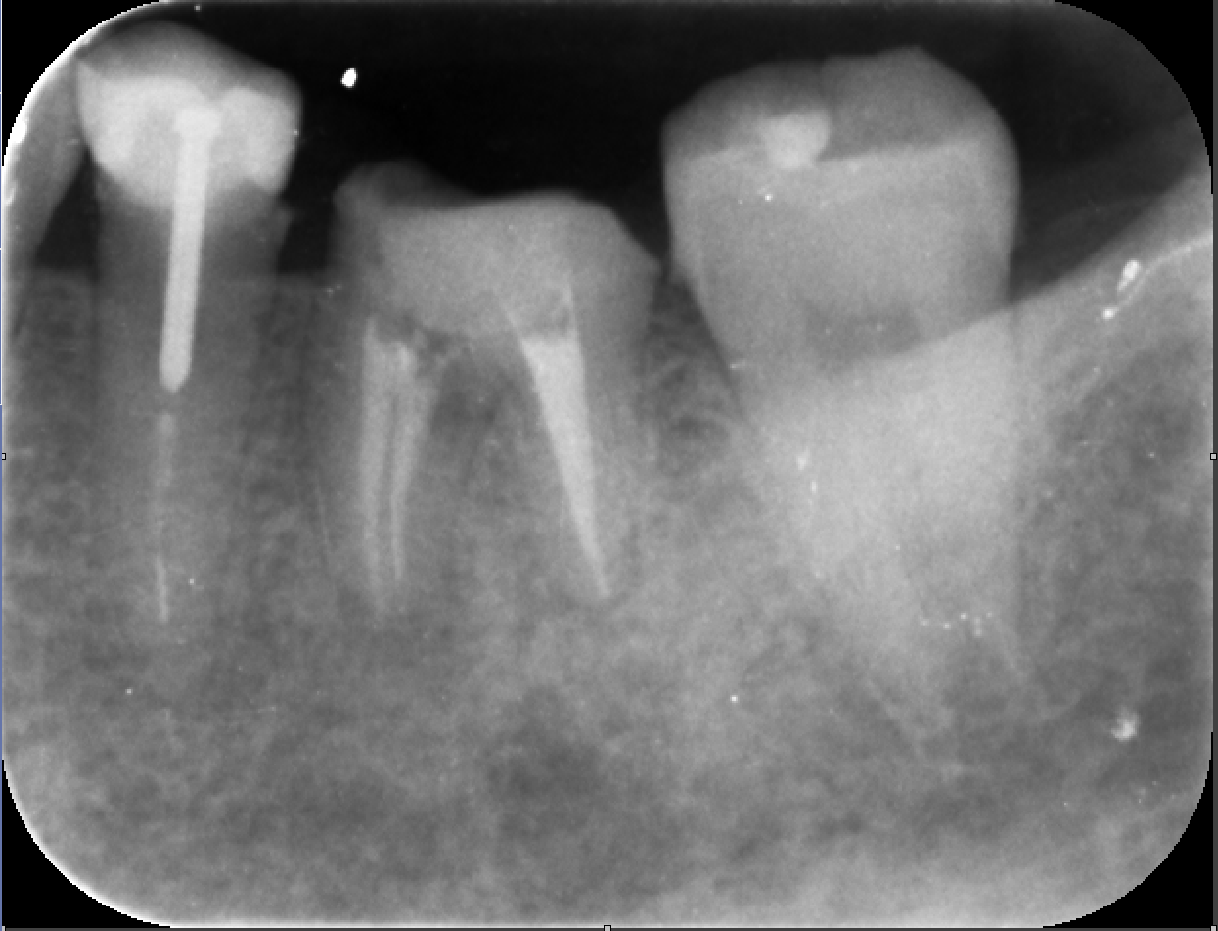

主訴:他院で1年根管治療していて不安。治らない。むむっ。根管充填が不良。これは痛そう。

精密根管治療で綺麗に。

根管充填 これでよくなるはずです。来年おいしいものを沢山食べれる様に!!